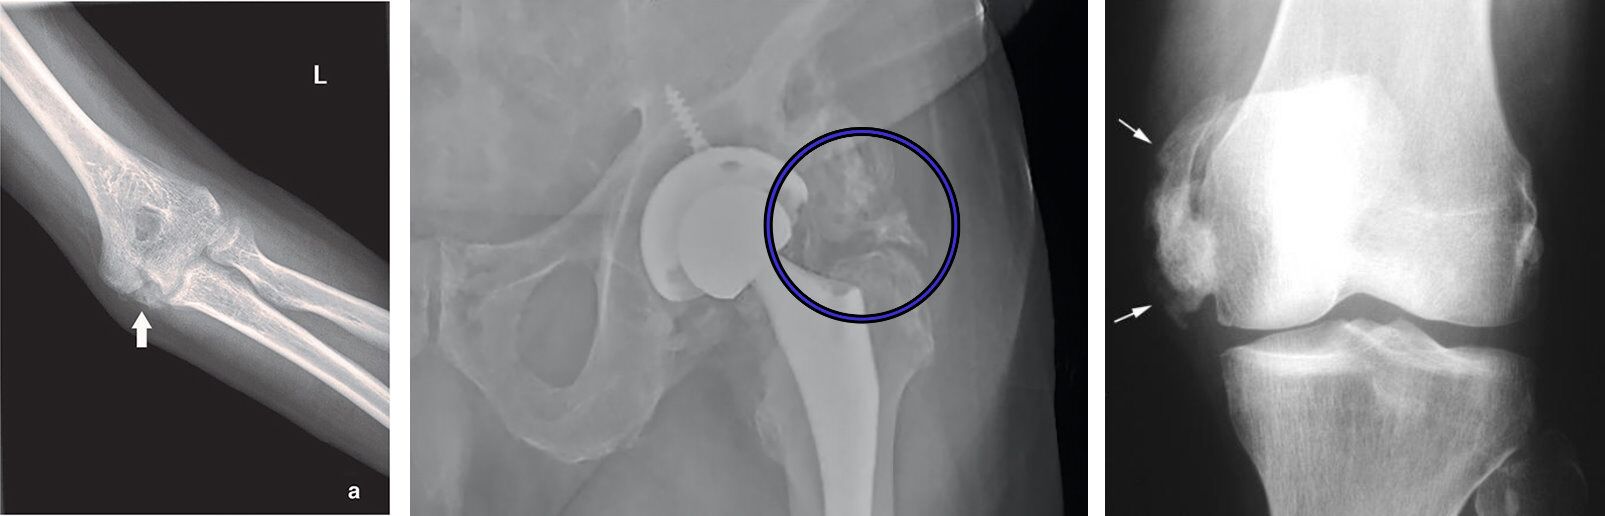

43.一位50歲的T8脊髓損傷患者在3年前受傷之後定期接受物理治療,最近患者開始抱怨膝部附近疼痛,治療師在觸診後發現膝關節附近有紅腫的現象,患者照了一張X光後結果如下圖。患者可能發生了什麼問題?

(A)關節攣縮

(B)骨化性關節炎

(C)異位骨化症

(D)痛風